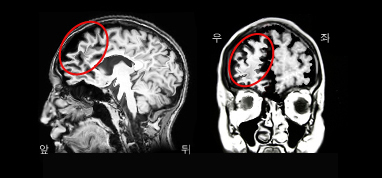

진행성 비유창성 실어증 환자의 MRI. 브로카영역의 위축이 두드러짐.

다른 치매와 마찬가지로 신경심리검사를 통하여 치매 여부를 판단하고, 그 아형을 분류한다. 또한 뇌 자기공명영상(뇌 MRI) 및 양성자단층촬영(PET) 등으로 다른 치매와 감별을 시도한다. 이마관자엽변성 환자의 MRI를 보면 이마관자엽치매(FTD)는 전두엽의 위축이 두드러지고, 의미치매는 측두엽의 위축, 그리고 진행성비유창성실어증은 브로카영역의 위축이 뚜렷하다.